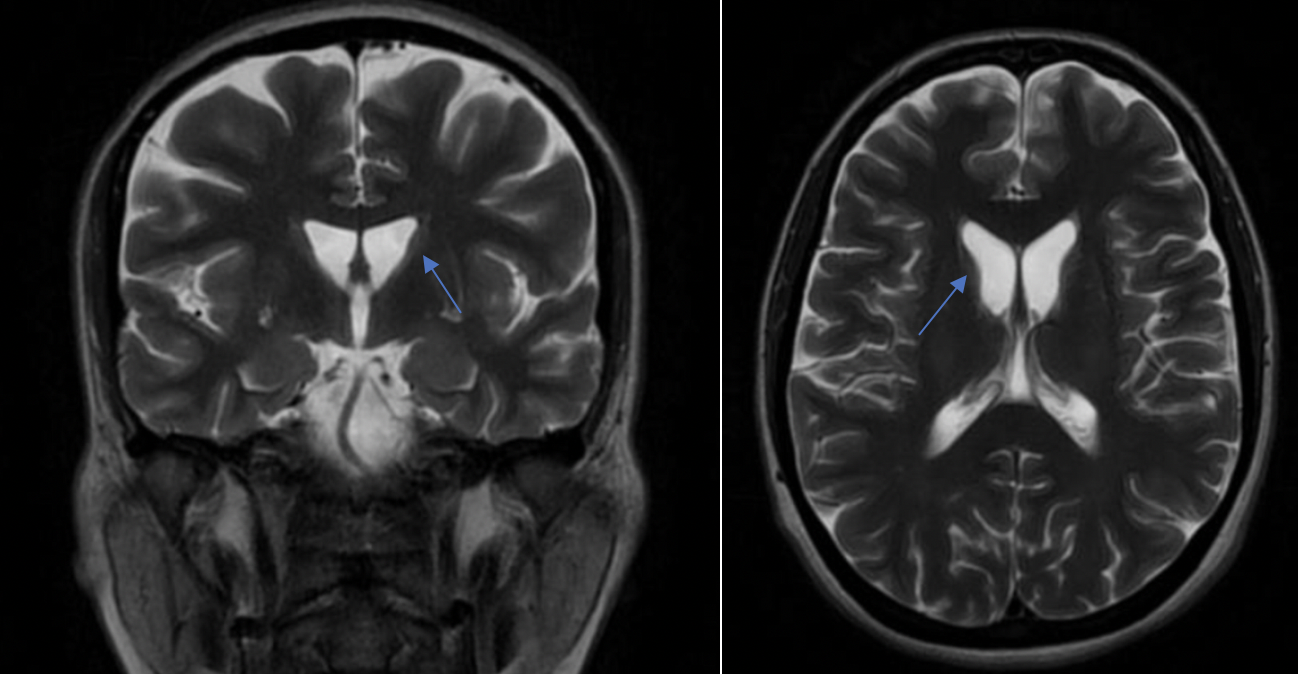

Results: A 34-year-old female, with healthy non-consanguineous parents, presented an obsessive-compulsive disorder for 5 years, 2 years later she presented spasmophemia, vocalizations and frequent lip biting with self-mutilation. Neurological examination revealed dysarthria, orolingual dyskinesia, mild generalized chorea and unsteady gait. Cognitive evaluation reported diminished attentional and executive functions. Laboratory showed presence of acanthocytes in peripheral blood film and CK levels >1000 U/L. EMG and echocardiogram were normal. MRI showed bilateral caudate atrophy (figure 1). HTT testing and copper levels were normal. NGS panel reported two heterozygous variants in VPS13A a deletion (Exons 51-59) classified as likely pathogenic, and c.5157C>T; p.Gly1719 = classified previously as variant of uncertain significance (VUS), but recently reclassified as likely pathogenic (4). Parents testing demonstrated that variants were in trans and the two unaffected siblings carried no variants.

Brain MRI show bilateral atrophy caudate nucleus